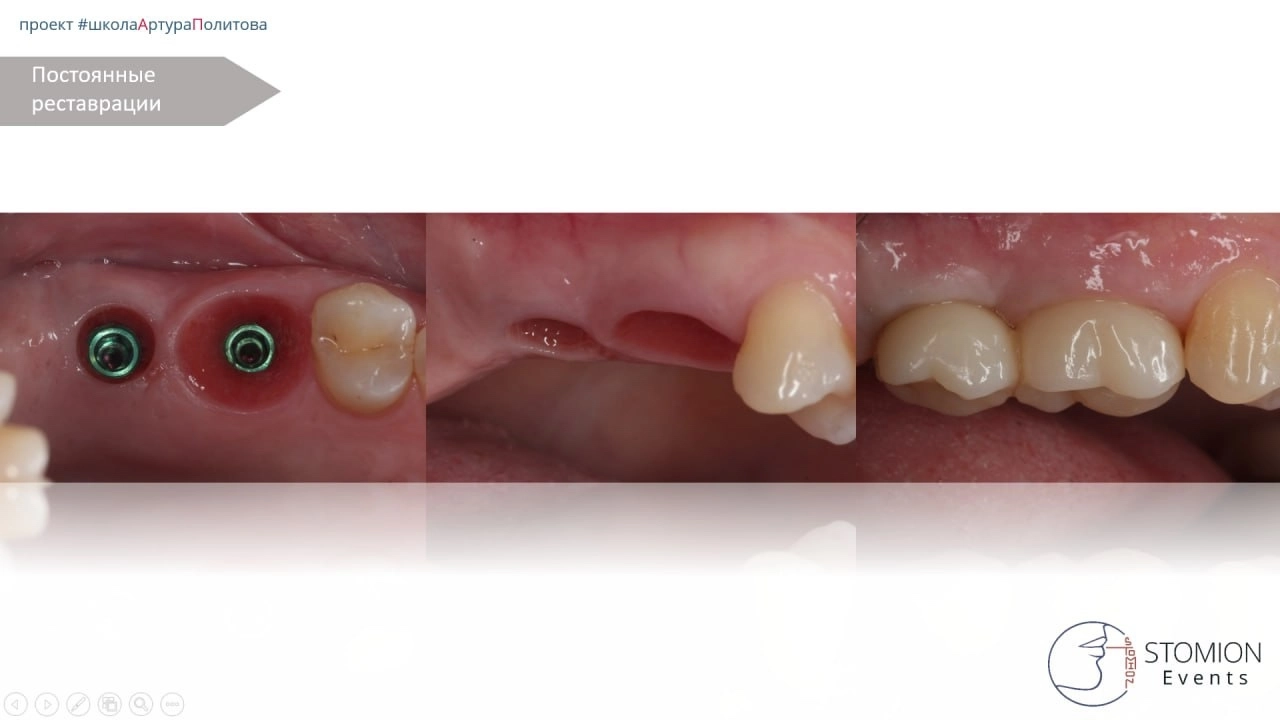

Результаты

— Через 3 месяца отмечена стабильная интеграция имплантатов в обеих позициях. Изготовлена постоянная ортопедическая конструкция.